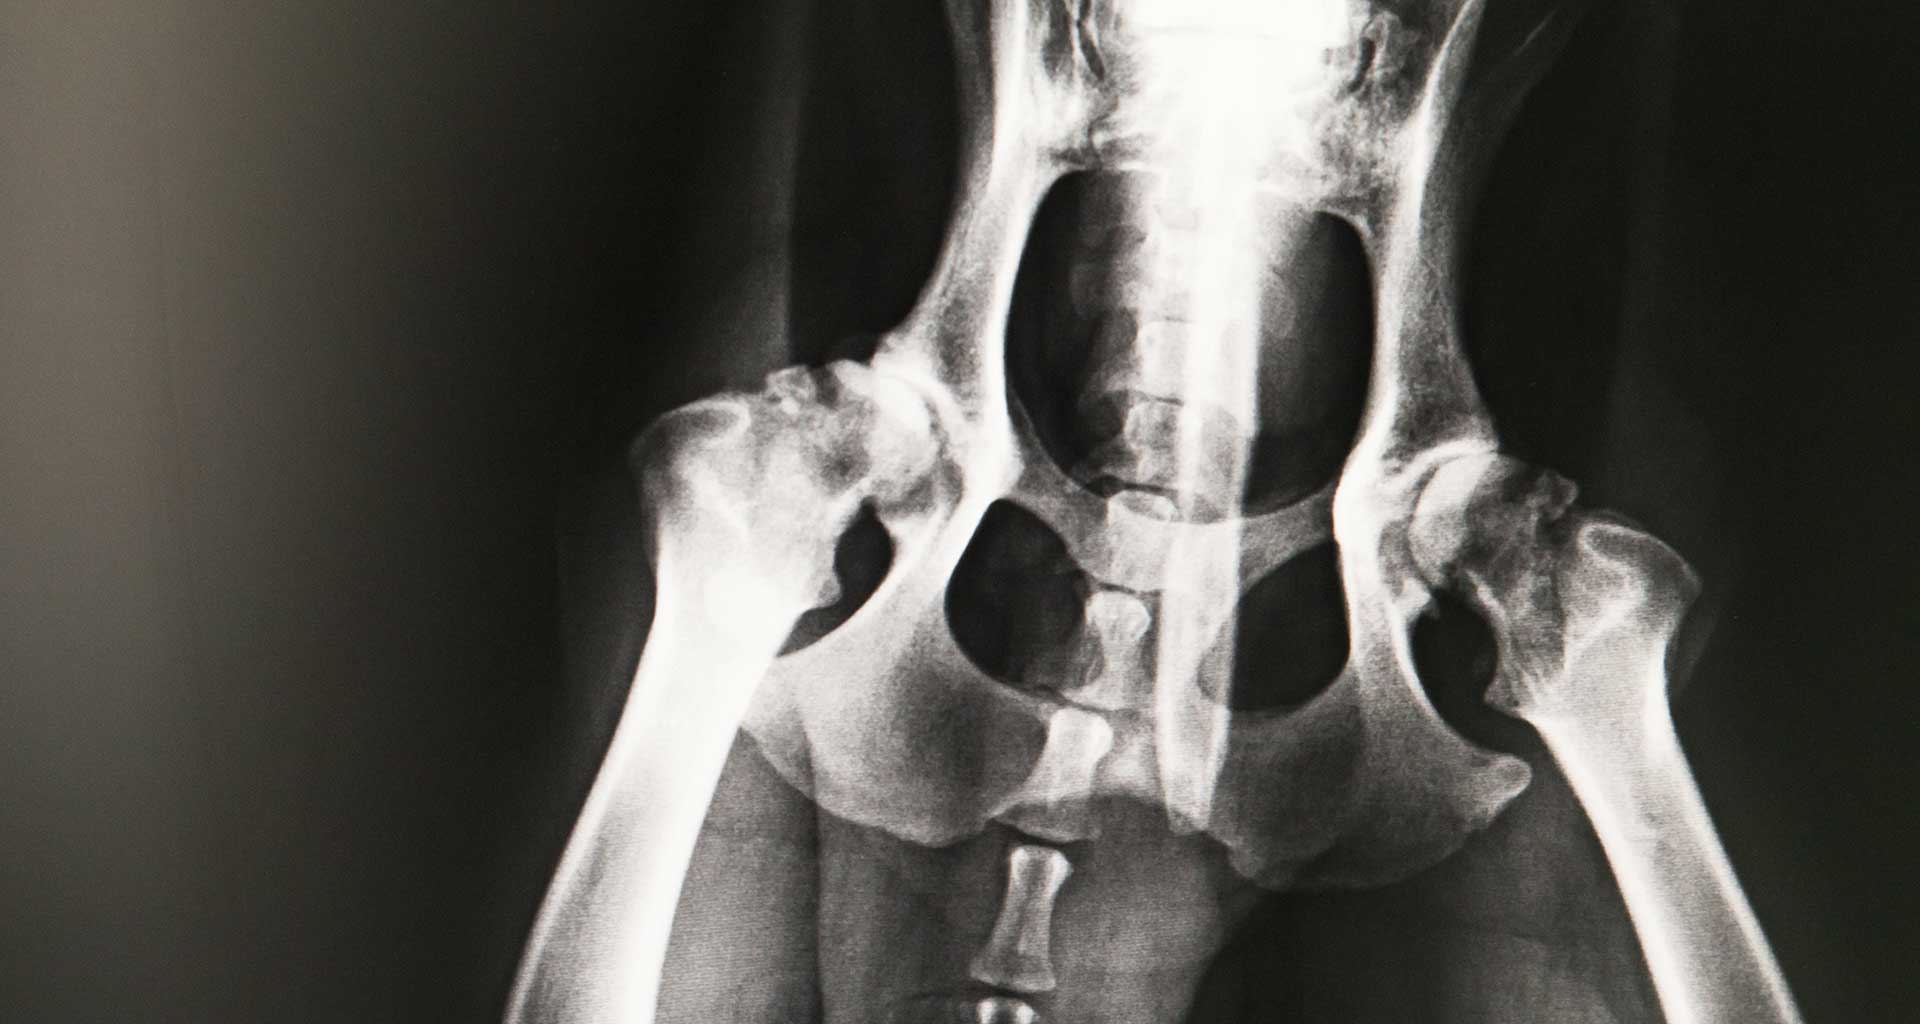

Radiographs (X-rays) are extremely important for accurate diagnosis and ruling out causes of certain diseases. Our vet clinic has skilled professionals who are able to use this technology to find the best solutions to your pet’s condition, often with near immediate results.

The main use of radiology is to determine if your pet is suffering an internal disease such as bone fractures, abnormal pathologies or lung disease. The veterinarian will then read the radiographs in order to diagnose any abnormalities. Radiology is based around the concept of diagnosing a disease in real-time to treat it fast and effectively.